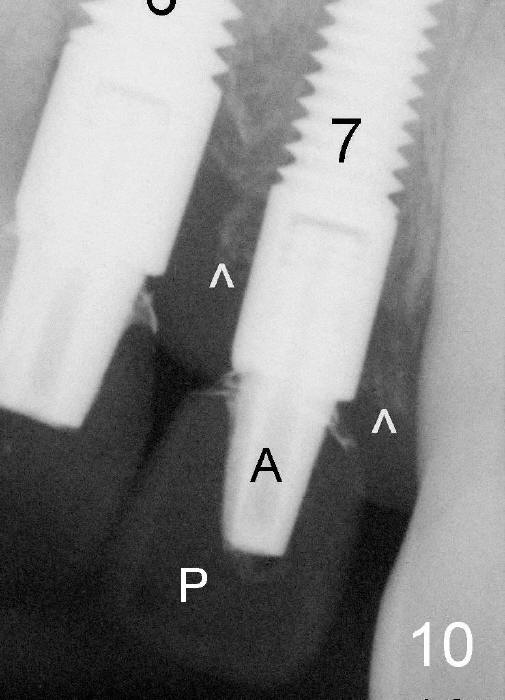

Fig.10: Six months postop. A: abutment (#6: 4x5 mm; #7: 3x5 mm); P: provisional.